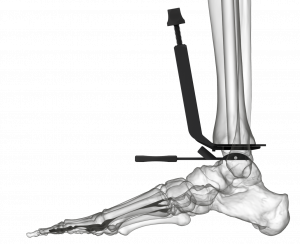

(Figure 5) The instrumentation to prepare the tibia for vertical peg and cage orientation is unique and simple to use (Figure 6); the Advita engineering team was brilliant in creating this impaction system disproving many doubters, including myself, that such an impactor could be safely introduced despite the ankle joint’s relatively limited access. The Vantage talar component’s backside has a uniform curve that optimizes compressive forces on the prepared dome-shaped talus throughout the ankle’s full range of motion. In contrast, nearly all competitors’ talar components provide alarm component stability via chamfer cuts that tend to create the potential for shear stresses. (Figure 5) One recently released total ankle system, features a uniform dome-shaped talar preparation like that of the Vantage but requires a lateral approach and fibular osteotomy for component implantation. The Vantage’ talar component confers the same talar component advantages via the far more commonly used anterior approach and does not require a fibular osteotomy. Unique to the Vantage total ankle system, a simple manual rasp is used to complete the uniform talar dome preparation.

Our ankle design team spent the better part of four years devising and perfecting the Vantage surgical technique. Our initial thoughts favored sophistication and complexity to confer advantages over the competitors’ ankles. However, complexity and its accompanying frustrations soon gave way to simplicity. The current surgical technique and instrumentation is remarkably straightforward. I recently taught a Vantage cadaver lab to a group of residents; none of the residents had prior experience performing a total ankle replacement. I can confidently state that the residents’ implanted Vantage ankles were on par with the first Vantage cadaveric ankle implantations of nearly every experienced foot and ankle surgeon at our training labs. The external tibial alignment guide is reliable in properly orienting the tibial cut, and punching the relief areas for the tibial component pegs and cage is easily learned. Talar preparation is uncomplicated, with reproducible positioning of the talar component in both the coronal and sagittal planes (Figure 9); creating the uniform talar dome arc is facilitated by the user-friendly manual rasp.